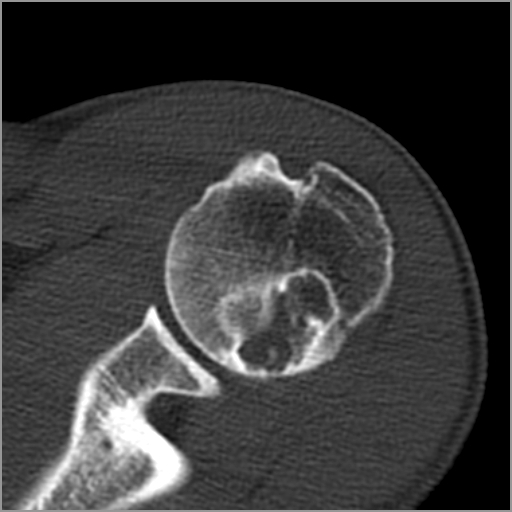

以下是引用zxd95在2008-7-19 18:45:00的发言:[br]囊性病灶边缘硬化、皮质变薄但连续——提示生长时间长、良性病变——考虑左肱骨头骨囊肿。[br]

以下是引用杀毒软件在2008-7-19 18:55:00的发言:[br]考虑:骨巨细胞瘤可能性大